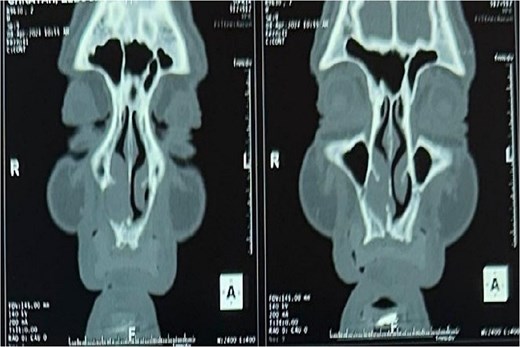

A CT scan revealed a mass centered on the right inferior turbinate, with no bony involvement but a polypoid filling of the right maxillary sinus, raising concern for malignancy (Figs 2 and 3).

Tomography image of the paranasal sinuses in coronal slice with parenchymal window revealing a tumoral-like mass in the right nasal cavity, centered on the right inferior turbinate.